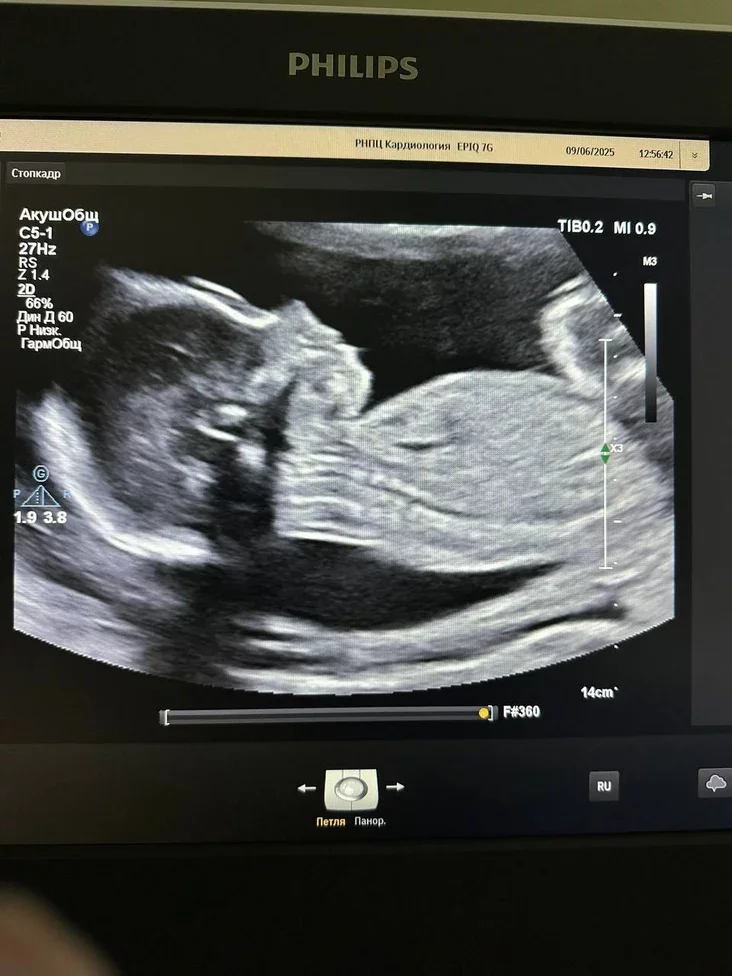

Как пояснили в ведомстве, это была первая такая операция в истории белорусской медицины. В июне 2025 года, когда ребенку было всего 23 недели от зачатия, врачи обнаружили в левом предсердии женщины миксому — доброкачественную опухоль, которая могла вызвать тромбоэмболию, инсульт или инфаркт и угрожала жизни и матери, и ребенка.

Чтобы удалить образование, специалисты провели сложную операцию на открытом сердце с использованием искусственного кровообращения. Благодаря слаженной работе команды из РНПЦ «Кардиология» и РНПЦ «Мать и дитя» на 23‑й неделе беременности угрожающую ситуацию удалось успешно разрешить. Операцию проводил кардиохирург Евгений Костюкович.

По информации Министерства здравоохранения, операция и послеоперационный период прошли без осложнений. Женщина безопасно доносила беременность до 38 недель. 2 октября ей сделали плановое кесарево сечение, и на свет появился здоровый мальчик весом 3230 граммов и ростом 52 сантиметра.